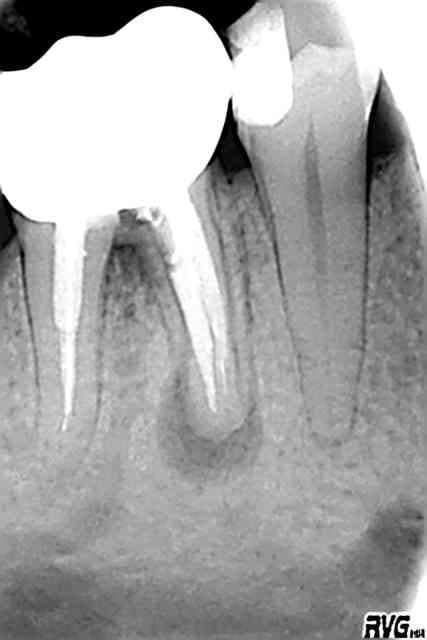

Avant 24062003 ex7dhe - Eugenol

Apres 25022005 blbnb9 - Eugenol

Al tu exagères, tu as inversé les radios.

Je te jure que c'est vrai. La date dans le nom des radios est exacte.

J'e ne suis moi-même, pas encore revenu de ce succès, alors que je n'avais apparemment pas obtenu la perméabilité apicale.

Mais j'ai irrigué, irrigué et encore irrigué, à la seringue d'hypochlorite.

Ensuite condensation verticale à la gutta chaude. Et voilà le résultat.